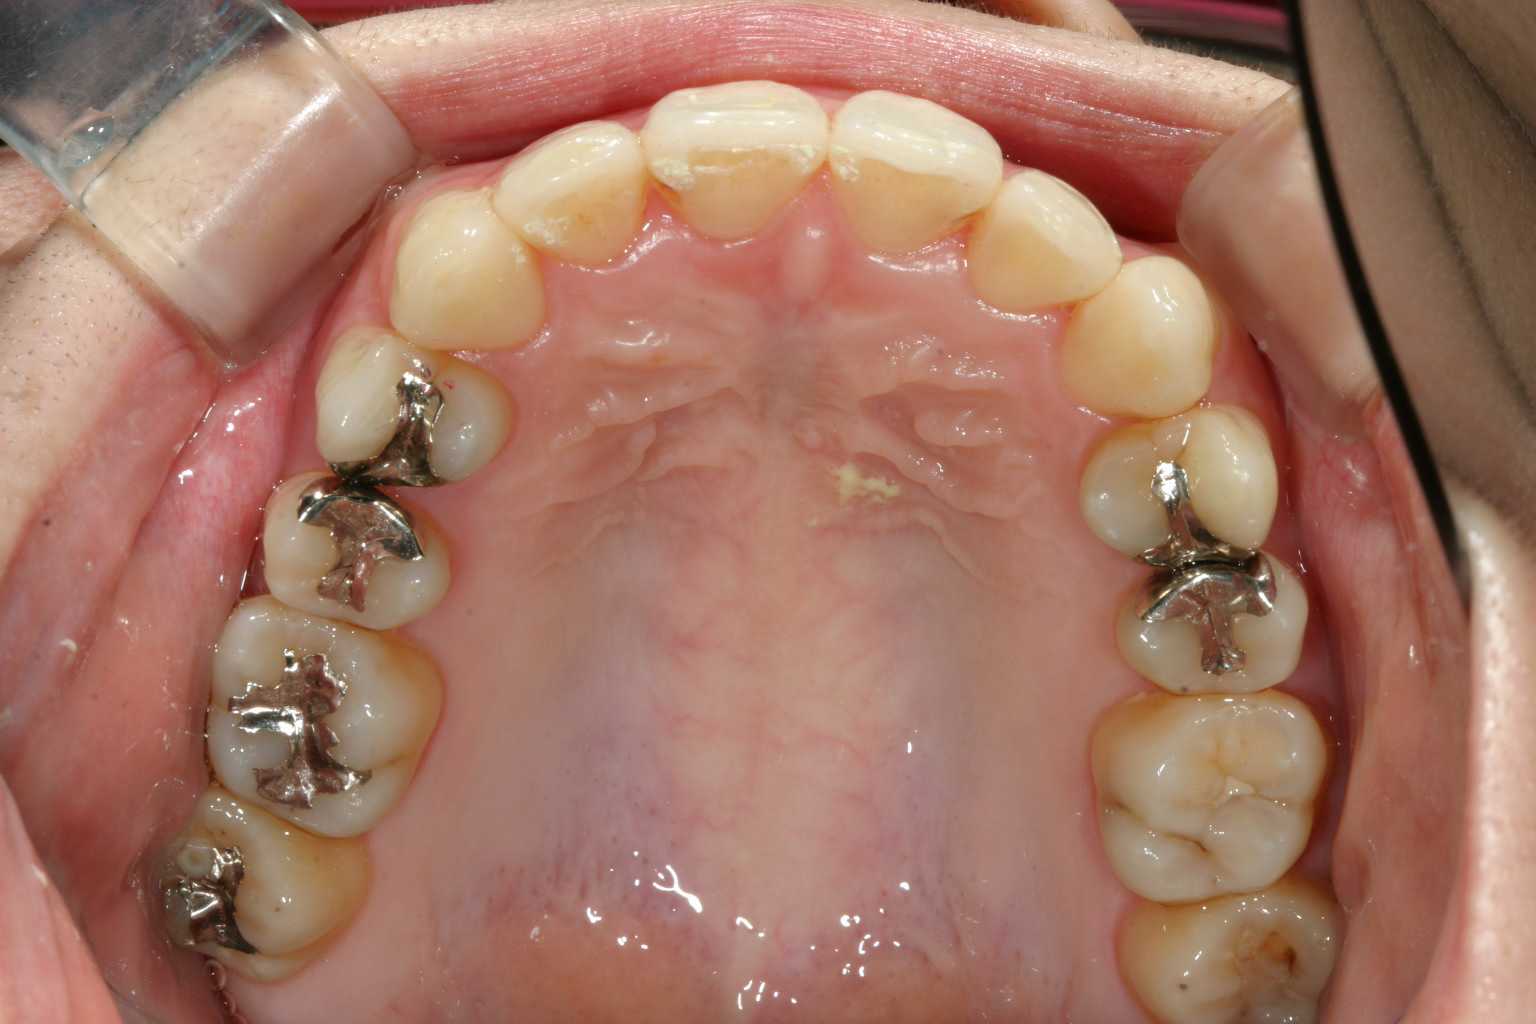

非抜歯でアーチも拡大され翼状捻転も改善しました。

抜群のオーバージェットが得られました。